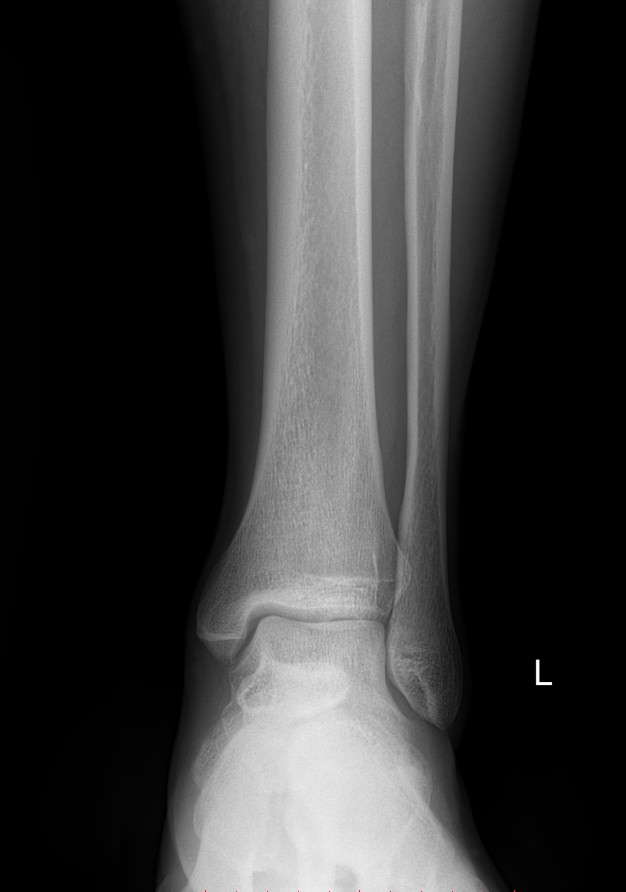

Голеностопные суставы отличаются сложным строением, в позволяющим стопе вращаться, сгибаться и разгибаться почти на 90о. Благодаря этому тело свободно перемещается в пространстве, меняет свое положение, поднимает собственный вес и дополнительный груз. Травмы голеностопных суставов встречаются также часто, как и хронические заболевания.

В качестве скринингового, а зачастую и единственного метода диагностики голеностопных суставов обычно используют рентген. Его вполне достаточно для визуализации внутреннего строения сустава и патологических изменений в нем. А цифровая нагрузка цифрового оборудования последнего поколения  несет минимум излучения и позволяет безопасно делать несколько снимков подряд.

Обследование обоих суставов с помощью рентгена помогает подтвердить диагноз, сравнить проявления на разных ногах, установить стадию заболевания, выбрать тактику лечения и определить его эффективность при следующих патологиях:

• Переломы и вывихи;

• Врожденные аномалии;

• Онкология;

• Дегенеративно-дистрофические заболевания.

• Изменения, произошедшие в костной ткани элементов суставов ― разрежение, некроз, озлокачествление, склерозирование;

• Нарушение четкости контуров костных образований;

• Перелом, его местоположение, смещение отломков;

• Состояние суставных щелей ― сужение, расширение, скопление жидкости, обызвествление капсулы;

• Конгруэнтность суставных поверхностей или вывих;

• Состояние мягких тканей ― отеки, инородные тела.